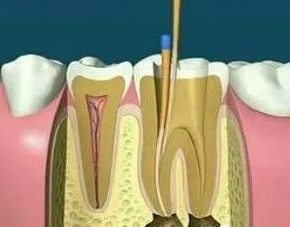

根管治疗,也称为牙髓治疗,是治疗牙髓疾病和根尖周疾病的有效方法。通过去除根管中的炎性牙髓和坏死物质并进行适当的消毒,填充根管以消除根管内容物对根尖周围组织的不利刺激,防止根尖周病变的发生或促进根尖周愈合病变。此操作可保护牙齿,因此可与拔牙互补。根管治疗很麻烦,通常需要2-4次就诊才能完成,并且患者会遭受更多的痛苦。

根管治疗的步骤

1、术前拍摄X线片:在根管治疗过程中,在根管治疗术前拍X线片,可以帮助诊断,了解髓室的位置和根管数目及形态,测量根管工作长度。

2、揭开髓腔:去净腐质和原有充填物、揭净髓顶,看到整个髓底解剖结构以便后续治疗顺利进行。

3、确定根管工作长度:应用平行投照X线方法、根管长度测量仪确定根管度,最好插针拍X片。

4、根管预备:根管清理成形的目的是去净根管壁上的感染物,通过根管器械的切削作用去除感染的牙本质并清理根管壁细菌以利于根管充填。

5、根管冲洗、消毒:根管冲洗的目的是清除微生物、冲掉残渣,润滑根管器械和溶解有机残渣。然后,再进行根管消毒,使根管内达到无菌状态。

6、根管充填:封闭整个根管系统、堵塞主根管和侧副根管出口、防止微生物和液体的渗漏。无论是侧方加压法还是垂直加压法,应做到根管充填致密,根管充填后X线片上无根管腔隙,也不能超出根尖孔。

7、根管打桩:因牙体缺损过多,导致牙的强度(承受力量的性能)大幅度下降,不能很好地承受咀嚼力量。打桩的目的是增加牙根及牙冠的强度,增加患牙的稳固。

8、完成牙体修复:X线片显示根管充填完好,行暂时或永久牙体修复,带上牙冠,保护患牙。至此根管治疗才可算完成,同时根管治疗后还需复诊,一般周期可为3个月、半年、1年、2年或更长。